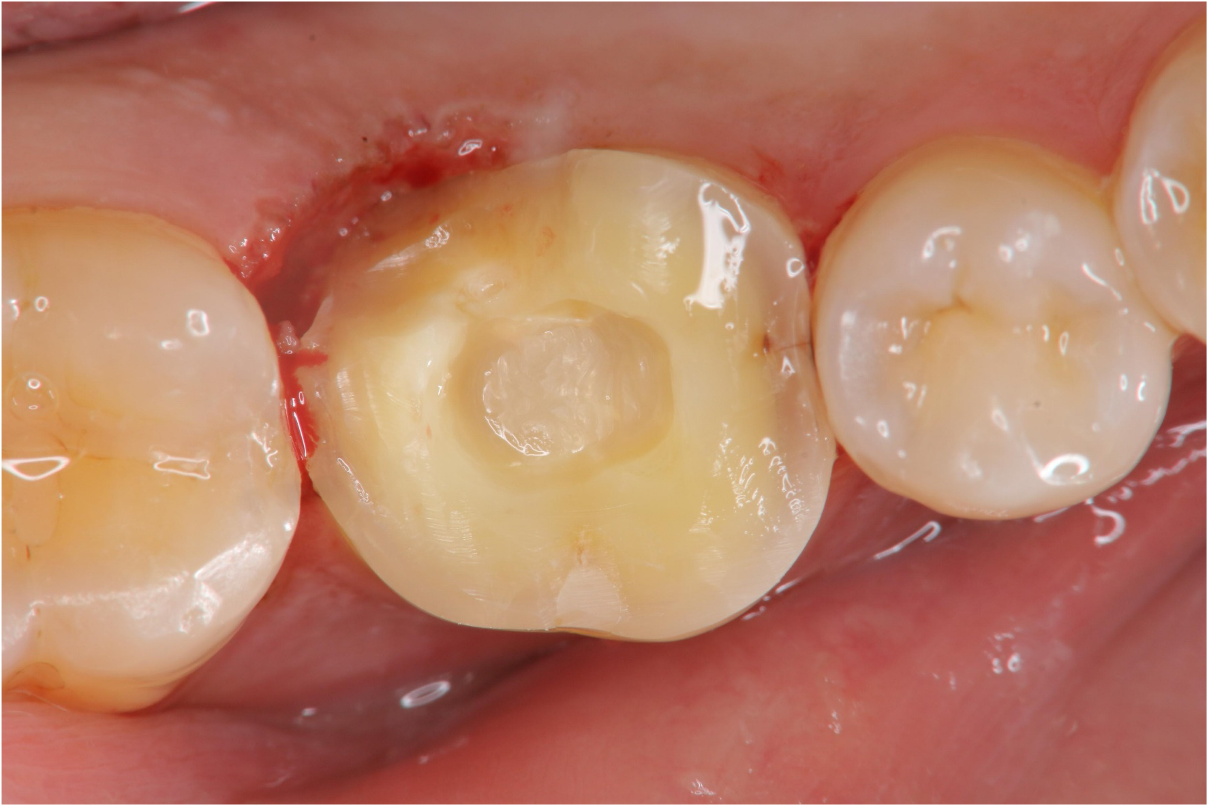

雷射切除牙齦,冠塊體製備